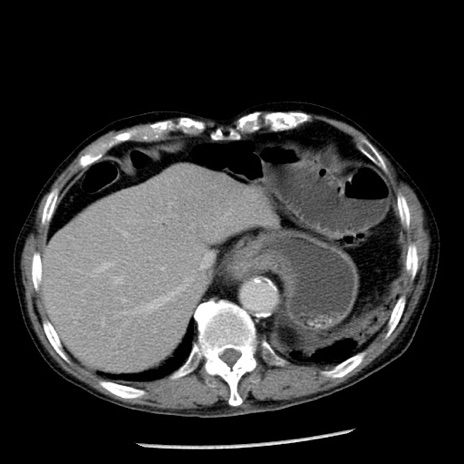

症例26(横断像)

【症例】80歳代男性

【主訴】嘔吐

【現病歴】昨晩2回嘔吐あり、今朝になっても嘔吐あり。来院。

【既往歴】胃潰瘍

【身体所見】意識清明、BT 37.6℃、BP 166/95mmHg、HR 100bpm、SpO2 97%、腹部:平坦・軟、腸蠕動音聴取良好、圧痛なし。

【データ】WBC 21900、CRP 1.46